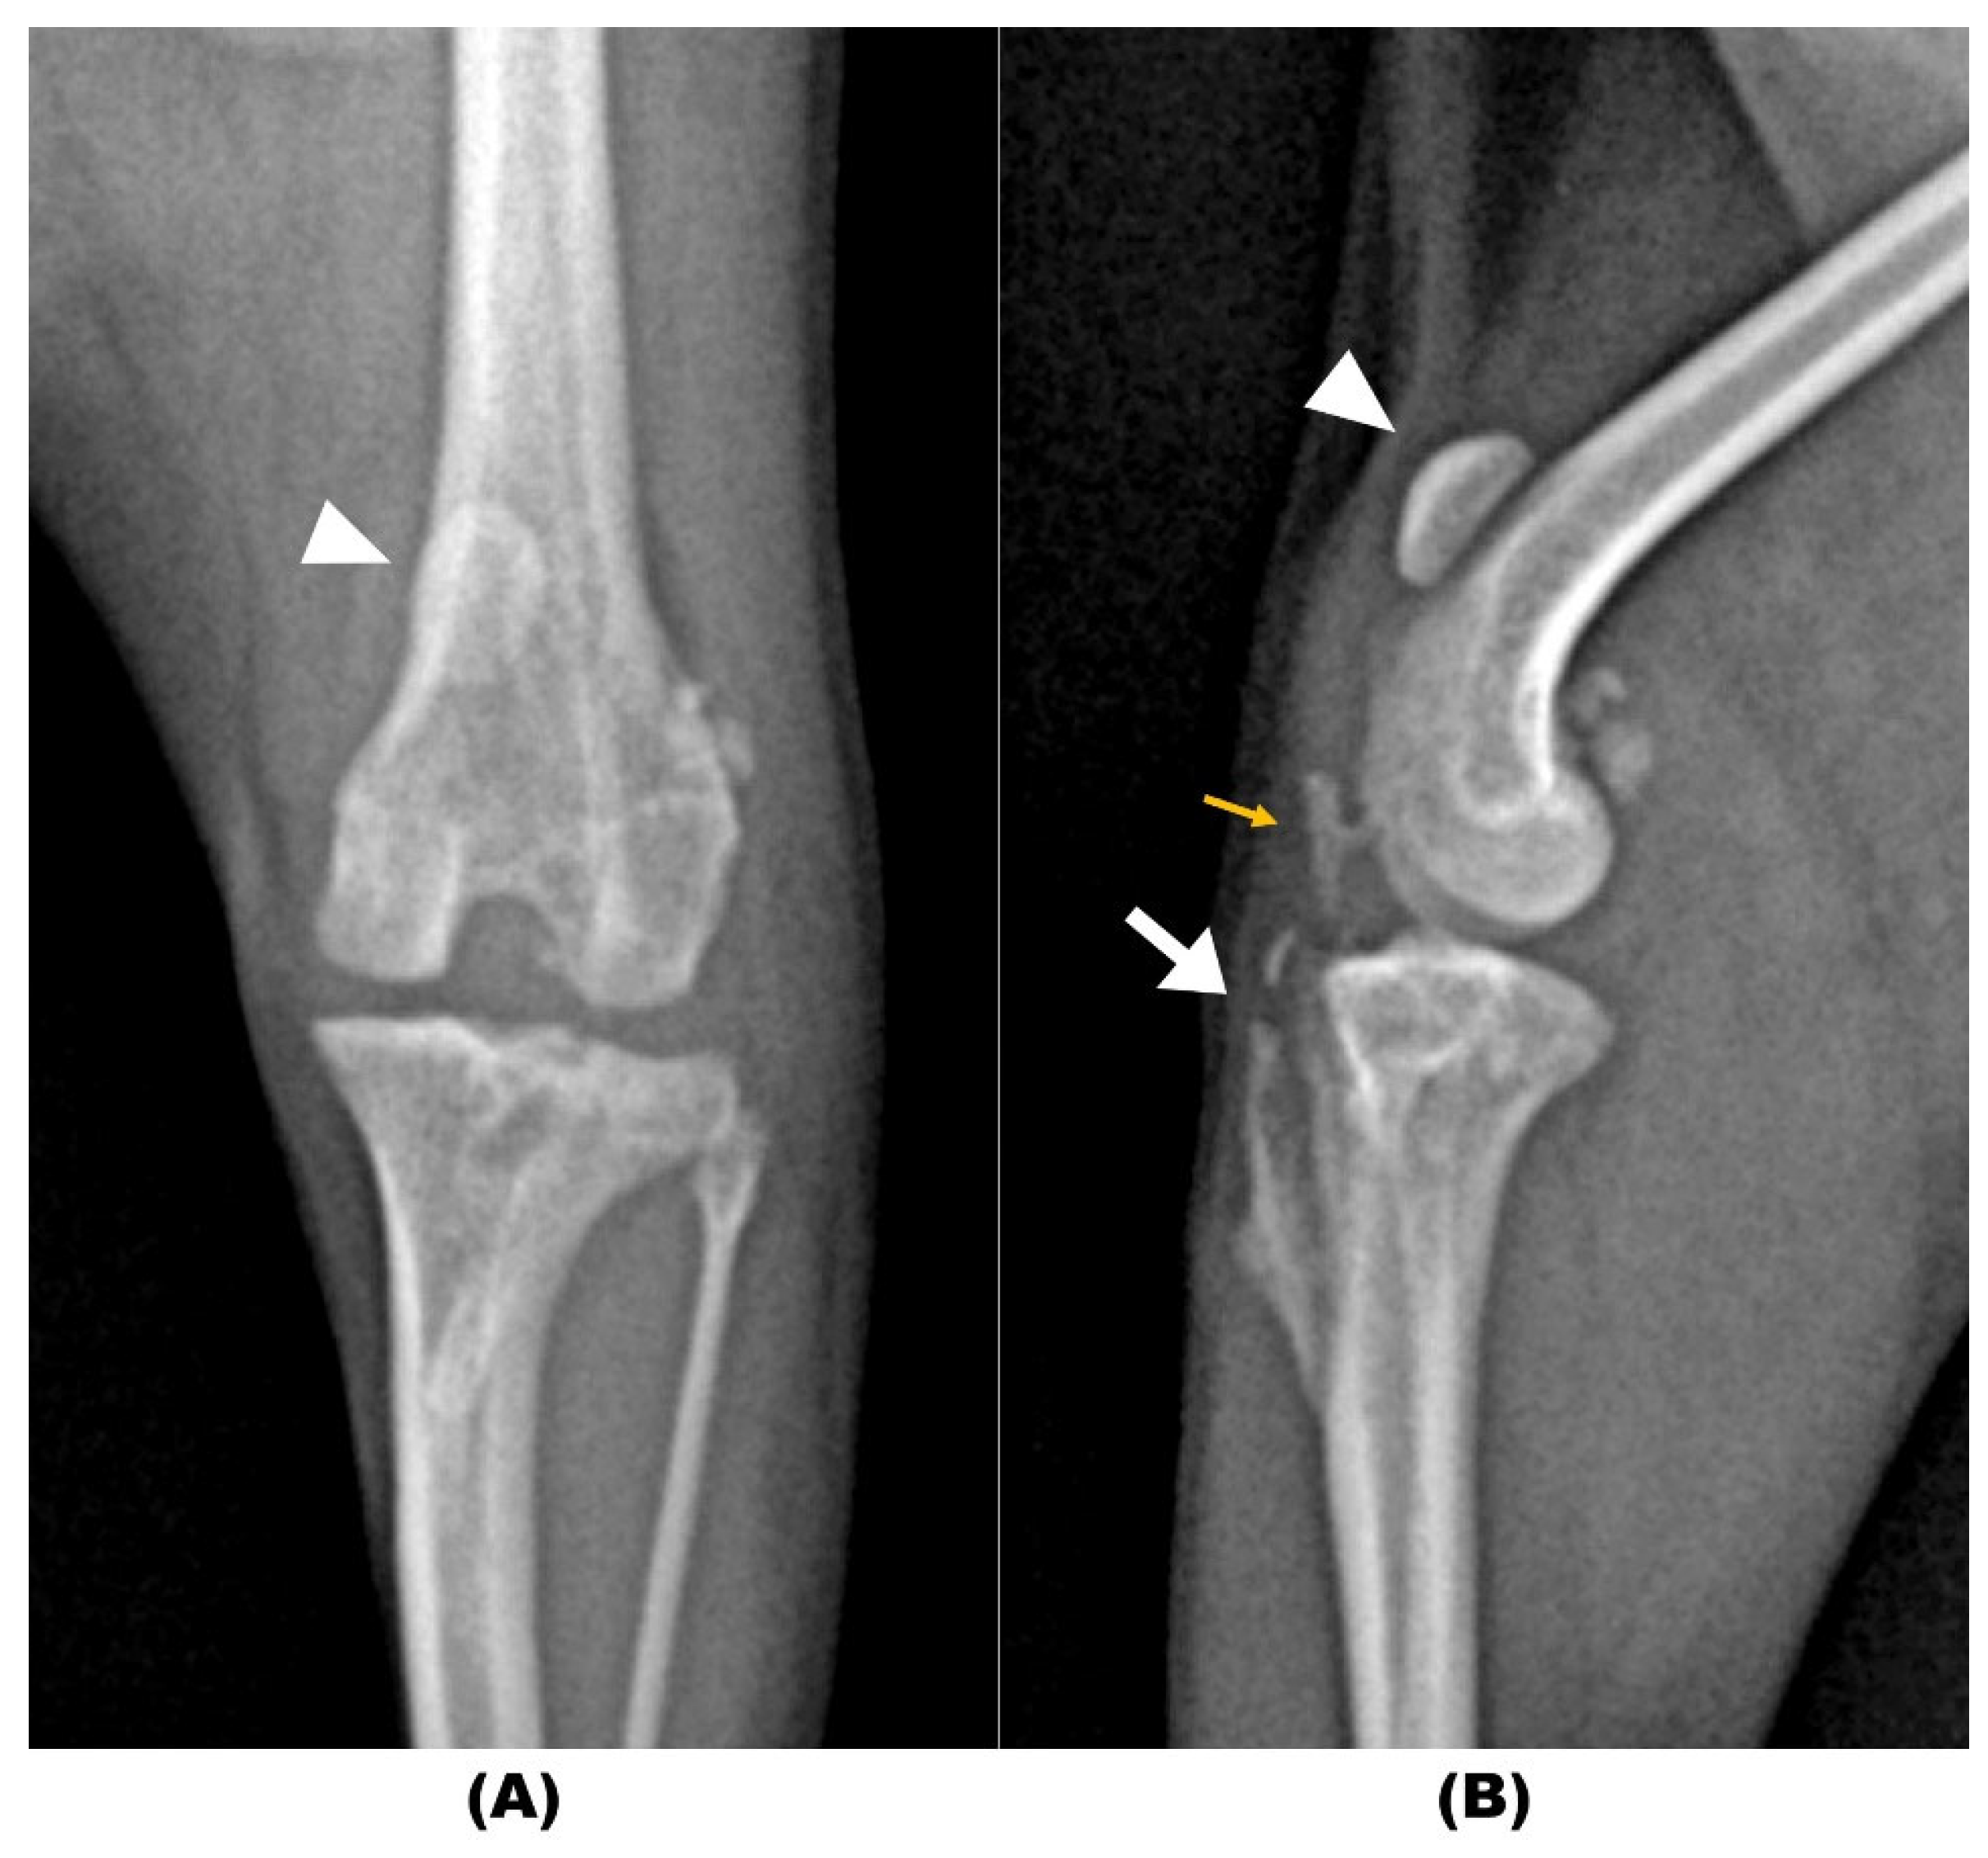

2. Case Description